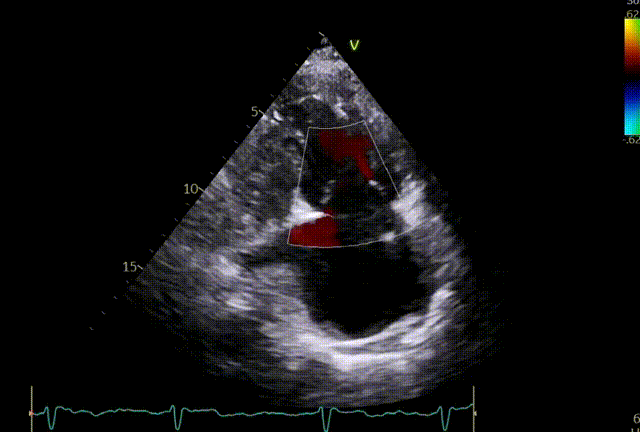

5.关闭夹子后超声评估。

术前

植入第一枚夹子后

1.反流效果:重度5+下降至轻度1+。

术后